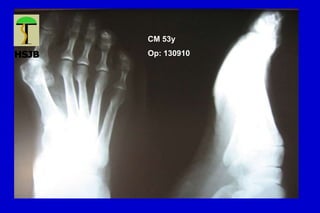

CM 53y

Op: 130910

HALLUX VALGUS

Desviación lateral del hallux, con varo del primer MT

Primer grado o leve Ángulo intermetatarsiano < 15ª

Ángulo MTF < 30ª

Articulación MTF congruente

Sublux sesamoidea mínima

Segundo grado o moderado Ángulo intermetatarsiano entre 15 y 18º

Ángulo MTF entre 20 y 40º

Subluxación MTF

Sesamoideo lateral luxado entre 70 y 100%

Tercer grado o severo Ángulo intermetatarsiano >18-20º

Ángulo MTF > 40º

Hallux pronado

Articulación MTF incongruente

Lx sesamoidea lateral del 100%